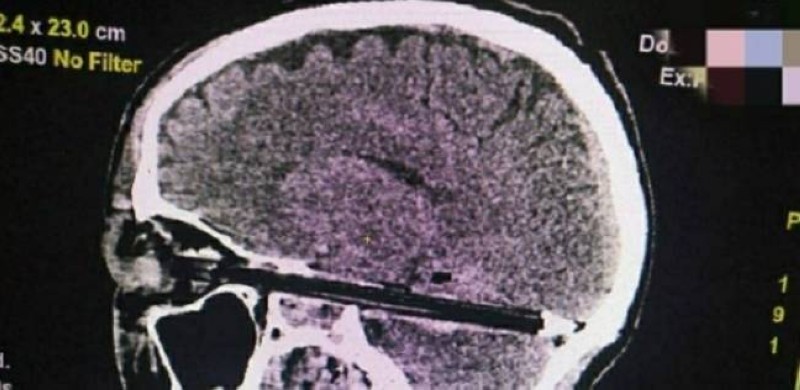

ووفق أطباء قسم الإسعاف بمنطقة روستوف الروسية، فإن القلم دخل العين بشكل كامل، ووصلت نهايته إلى مؤخرة الجمجمة، ومر مليمترات من الأوعية الدموية الرئيسية وجذع الدماغ.